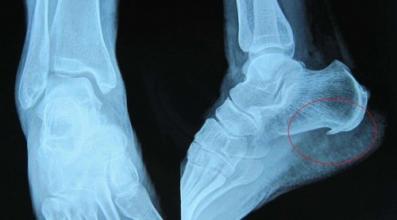

核心提示:距骨骨折较少见,多由直接暴力压伤或由高处堕落间接挤压所伤。后者常合并跟骨骨折。距骨骨折,易引起不愈合或缺血性坏死,应及早诊治。距骨骨折的饮食禁忌有哪些?下面我们一起来看看吧。一、距骨骨折的饮食禁忌  ...